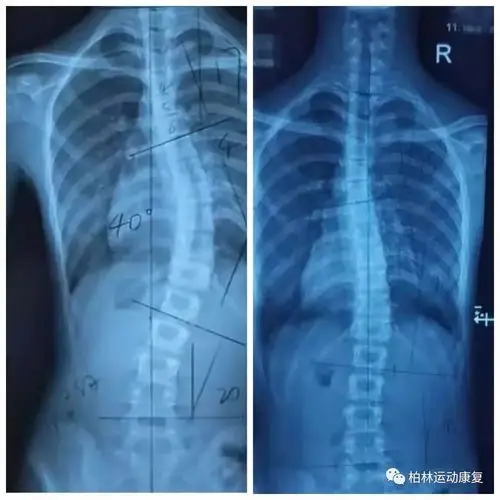

青少年体态康复脊柱侧弯全面解读与运动康复